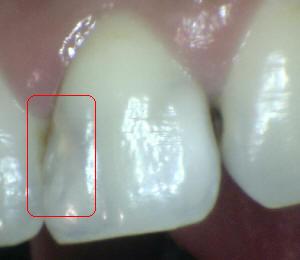

¿Determine los códigos pertinentes a cada imagen?

Click en el hipervínculo: Para comparar el resultado de su diagnóstico